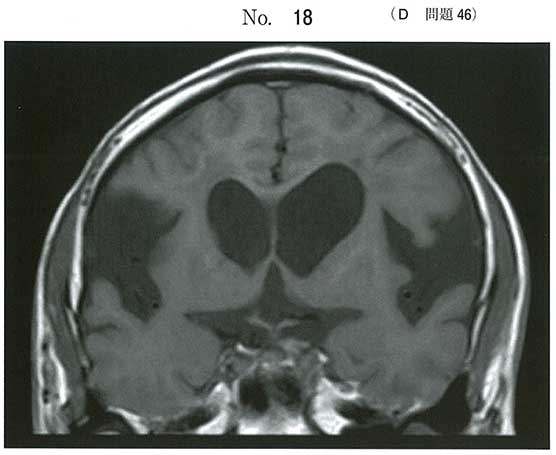

典型的なDESH(disproportionately enlarged subarachnoid-space hydrocephalus)の画像です。iNPH(idiopathic Normal Pressure Hydrocephalus)です。治療はVP shunt(Ventricular Peritoneal shunt)です。最終講義でのヤマ、当たりましたね!

NPH=>VP shunt 素直な問題だなあ~